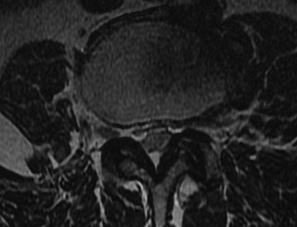

MRI

T2 Sagittal - myelogram

T1 Axial - see nerve root against white fat